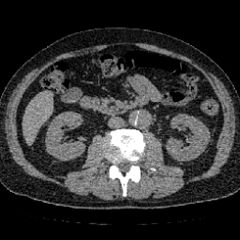

#大動脈解離に関するブログ新着記事です。主治医と久しぶりのご対面寸志の日のおっさんの独り晩飯 マグロ丼記録。今日の晩ご飯 ハナモクはさざえのつぼ焼き‼️(^^)激しい雨 の巻 評価順 7件中1~7件表示 大地と花 65才~男性 13年 1users 日記 薬剤 検査 手術 リンク 解離性大動脈瘤 上行大動脈解離性大動脈瘤 弓部大動脈人工血管置換術 ★★★ 乖離な日々 35~49才男性 12年 1users 日記 薬剤 検査 手術 解離性大動脈瘤急性大動脈解離 動脈は三層構造になっており、内膜、中膜、外膜で構成されています。 大動脈解離は、大動脈の内膜と中膜に亀裂が入り、裂けることでそこに新たな腔 (偽腔)が出来ます。 それが進行すると、分岐されている血管を圧迫、狭窄させ虚血